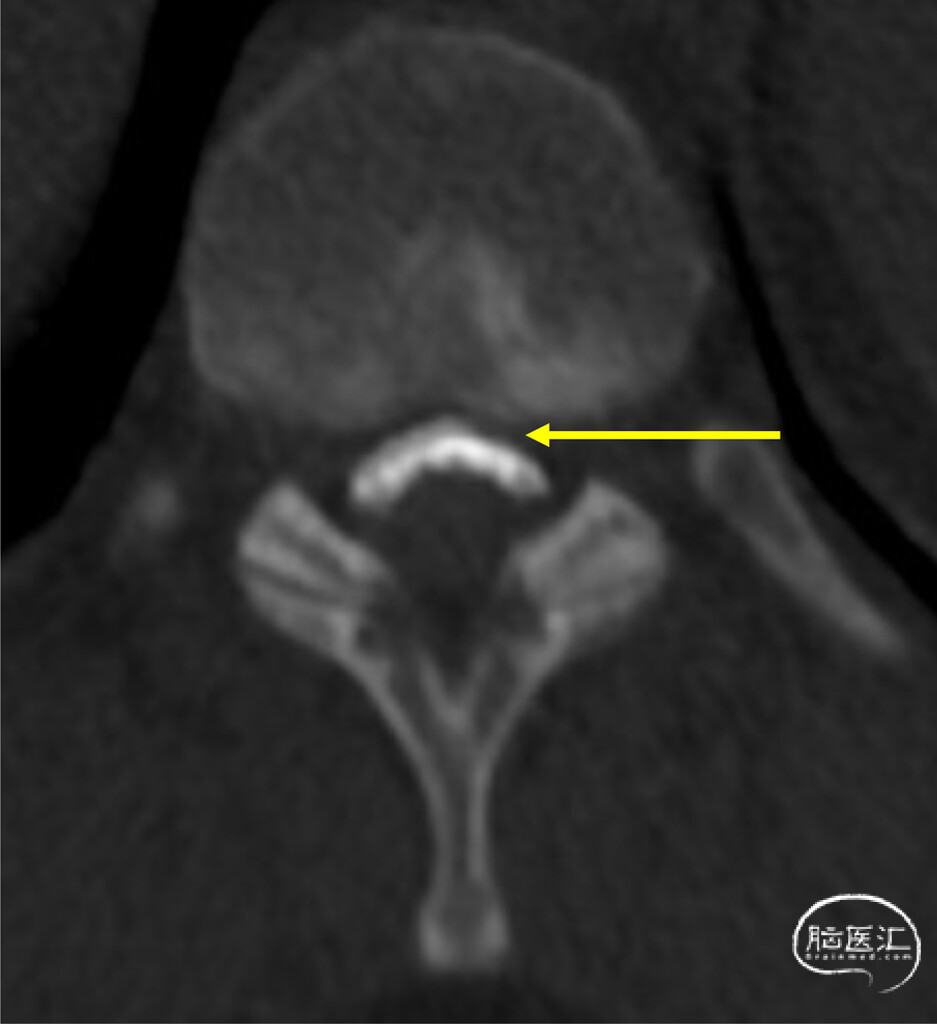

1.dCTM定位漏口:最初由尾侧向头侧扫描,未见造影剂立即外渗,提示不存在高流量漏。随后由头侧向尾侧扫描时,在T10–11节段中线偏右侧发现一处细微的腹侧造影剂聚集(图4),提示存在硬膜缺损及脑脊液漏位置。延迟仰卧位扫描证实,边界清晰的腹侧硬膜外积液从T6–7延伸至T10–11,与既往检查结果一致。鉴于患者症状持续存在且已明确缺损位置,遂行开放性手术修补。

图4:动态CT脊髓造影显示,T10–11节段中线偏右侧可见微量硬膜外造影剂积聚(箭头所示)。